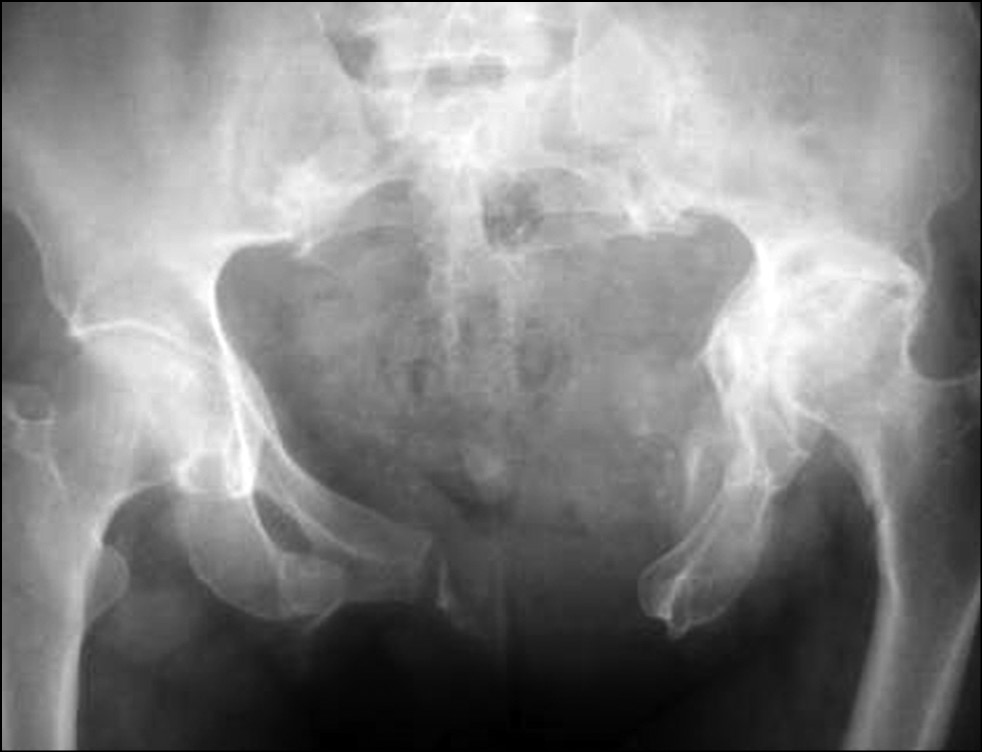

После обследования и подготовки пациента, принято решение о проведении металлодеза переднего полукольца таза реконструктивной пластиной (рис. 2).

Рис. 2. Рентгенограмма после операции

Fig. 2. X-rays after surgery